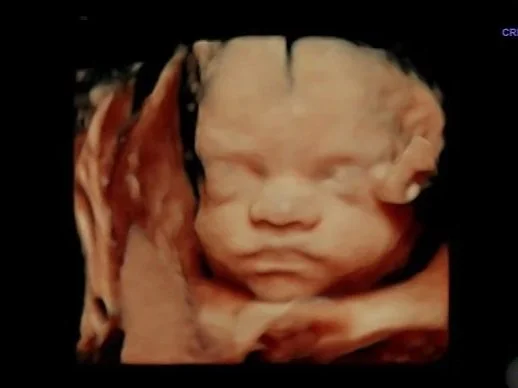

15-minute 3D/4D/HD Ultrasound

Looks best at 28 weeks+ but can be done as early as 15 weeks

This 15-minute appointment will feel very quick. The whole appointment will be spent trying to see baby’s face. (TIP if you know you have an anterior placenta, you don’t drink a lot of water on a normal bias, or baby is breech, this appointment may not be your best choice for seeing baby)

6 Ultrasound sound prints

Baby Position

Hear Heartbeat

$113

Come again and again for $80

To book this use the “returning visit” tab upon booking.